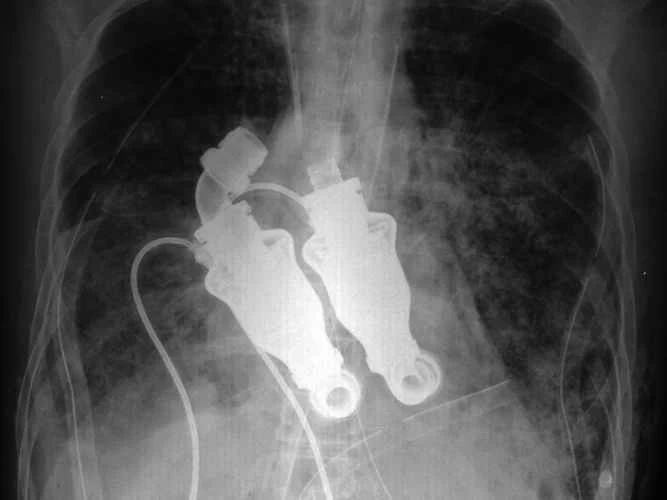

これらの身体部位の中には、既に利用可能で、命を救ったり、生活を楽にしたりするものもあれば、プロトタイプや概念実証の段階に過ぎないものもある。既存の身体部位を可能な限り犠牲にすることなく置き換えるように設計されたものもあれば、生身の肉体よりも優れた利点をもたらすものもある。これがバイオニクスの現状、そして近未来の姿である。